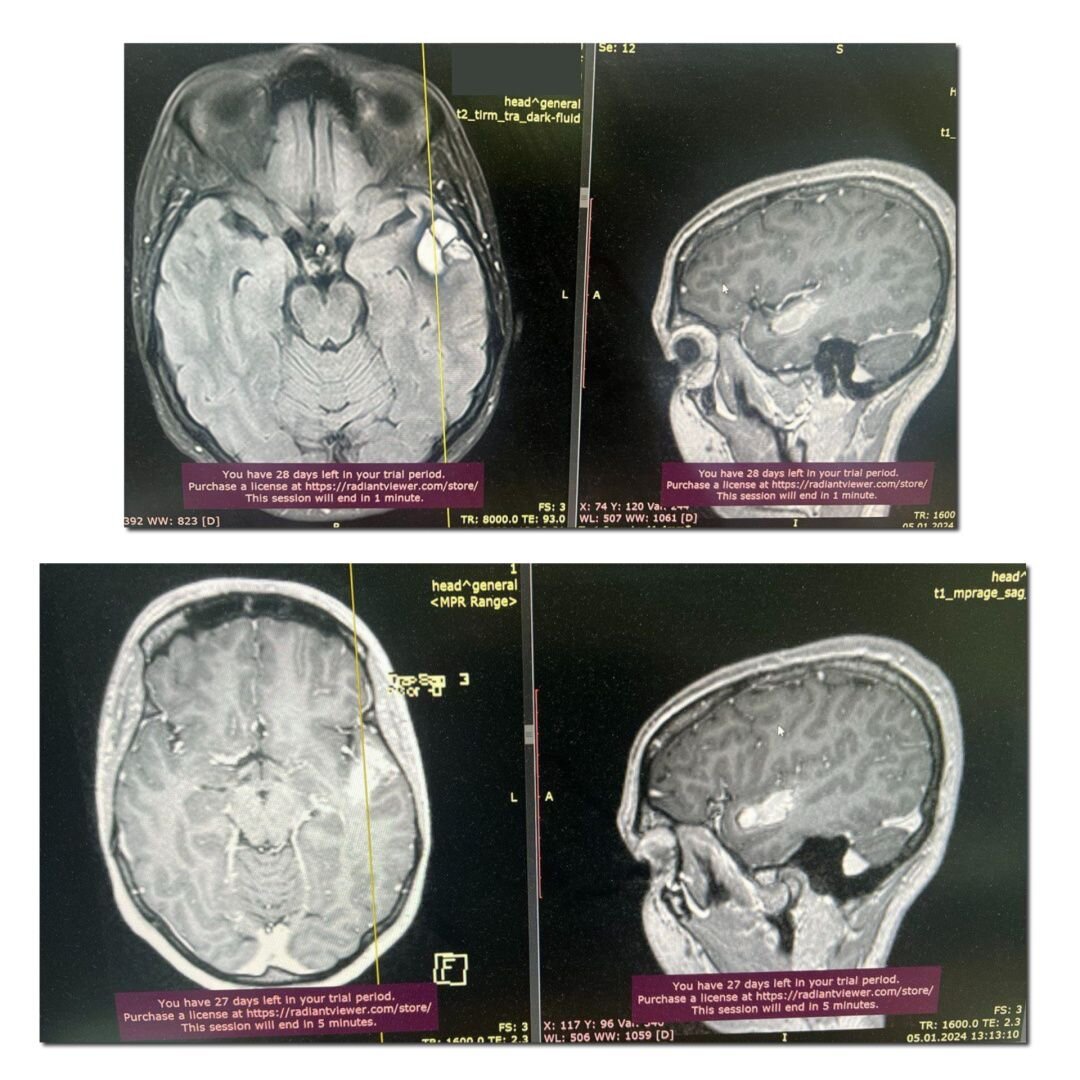

Удаление доброкачественной опухоли головного мозга, из-за которой произошел инсульт

При обследовании на МРТ была обнаружена кавернома. Это такое сосудистое новообразование головного мозга, сформированная из сосудов, которая очень часто дает кровоизлияния (как и произошло в этом случае). Обратите внимание - кровоизлияние является показанием к хирургическому вмешательству при этом диагнозе. Была выполнена краниотомия и микрохирургическое удаление опухоли с помощью операционного микроскопа и микроинструментов.

Пациентка выписана на 5 сутки после операции. А на 10 день она уже пришла снимать швы.